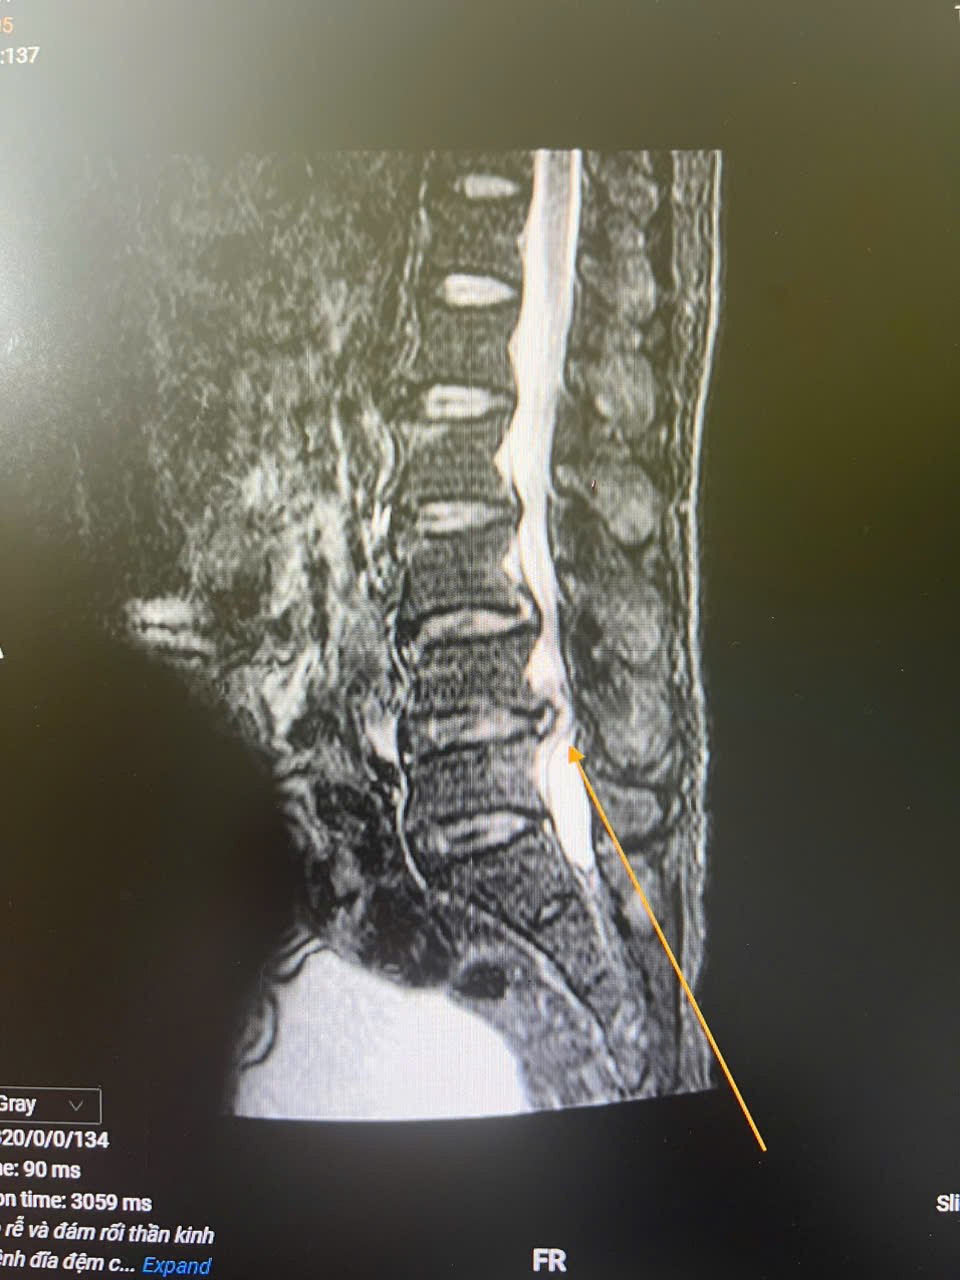

Ảnh 1: Cảnh báo biến chứng nguy hiểm từ thoát vị đĩa đệm, hẹp ống sống

Qua thăm khám và chẩn đoán, các bác sĩ xác định bệnh nhân mắc thoát vị đĩa đệm kèm hẹp ống sống và rối loạn cơ tròn – tình trạng nguy hiểm, có thể dẫn đến liệt vĩnh viễn và mất chức năng đại tiểu tiện nếu không can thiệp kịp thời. Bệnh nhân đã được chỉ định phẫu thuật.